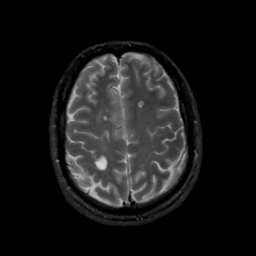

MR Study #15, June 9, 1991 -- Slice #38